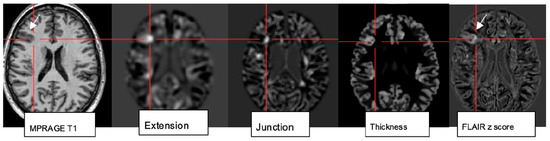

While visual analysis alone based on higher signal and spatial resolution increases the conspicuity of small pathologies, combination with postprocessing techniques (normalization, segmentation, and subtraction/division from a database of normal controls) and submission to a morphometric analysis program proved particularly beneficial to identify lesions that are beyond immediate visual recognition [78]. The morphometric maps created within the morphometry analysis program (Figure 6) encompass the MRI hallmarks of focal cortical dysplasia: abnormal extension of gray into white matter and configuration of deepened sulci, abnormal thickening of the cortical ribbon, and blurring of the gray–white matter junction. These are used to create morphometric extension, thickness, and junction maps. The “combined map” represents the maximum z score of the three maps for each voxel but is still finally verified by visual analysis [79].

Figure 6.

Morphometric analysis by normalization, segmentation, and subtraction/division from a database of healthy controls results in the calculation of z score maps: extension corresponds to abnormal gyration/sulcation, location of gray matter (GM); junction signifies blurring of GM-WM border; and “thickness” depicting cortical thickening in a patient with right frontal FCDIIb (see MPRAGE T1, FLAIR z score image).

Rapid analysis of a 3D MP2RAGE dataset in conjunction with a side-by-side comparison of FLAIR sequences increases sensitivity and reduces false-positive findings by morphometry. The generation of probability maps for lesions such as FCD in the future will further benefit from the integration of artificial neuronal networks [80].